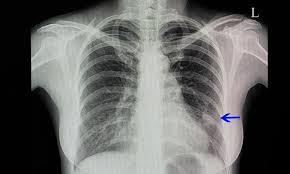

Die Lungenentzundung Ist Eine Schwere Erkrankung Die Nicht Einfach Zu Diagnostizieren Ist Gesundheit